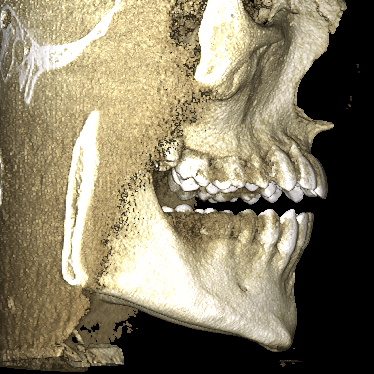

I have subhuman smile, I barely show any upper teeth when smiling, so got 3d scan done and results say a lot.

my maxilla itself isn't really short but bone above upper teeth specifically Alveolar process of the maxilla is extremely short compared to normal.

Im like perfect fucking candidate for lefort 1